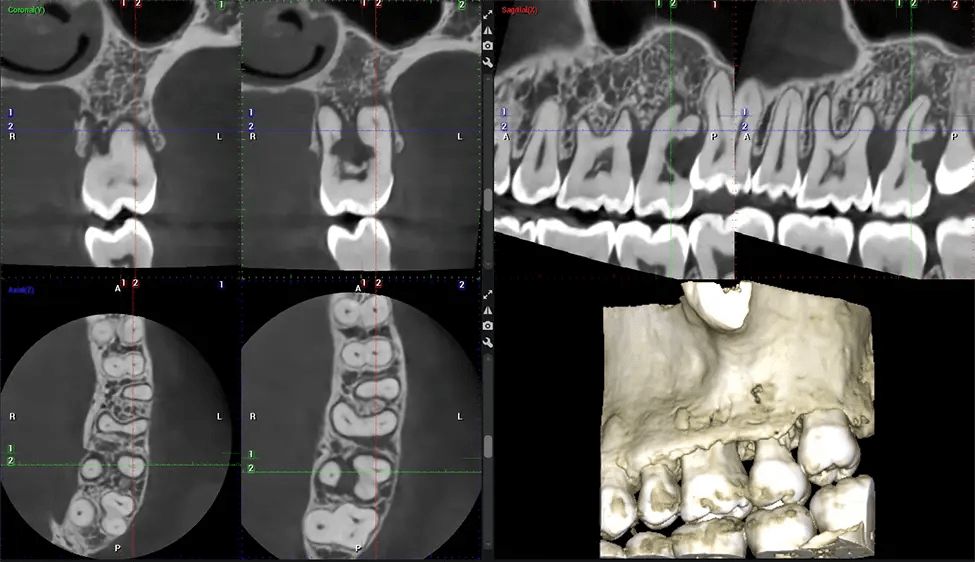

This 3D scan, called cone beam computed tomography, gives your dentist a more complete image of your oral anatomy and disease processes than a traditional X-ray. Unlike conventional X-rays, which capture a 2D image of your mouth from various angles, a 3D scan takes multiple digital X-rays for one image. It provides a complete view of your jaw, teeth, nerves, and soft tissues. This enhanced view allows dentists to detect minor issues not visible in traditional 2D scans, such as impacted wisdom teeth or bone fractures in the sinus cavity.

There are many benefits to using CBCT technology, especially compared to the traditional 2D X-ray format. One of the most significant advantages of CBCT scans is that they provide much more information than traditional X-rays. A scan lets your dentist see images from all angles of your jaw and mouth, including your sinuses, nasal cavity, cheekbones, and other surrounding areas. This added information helps your dentist craft a comprehensive treatment plan that addresses all aspects of your oral health.

Another significant benefit is that 3D imaging provides more precise images of your bone structure. These images are more detailed, providing you with a more accurate diagnosis. An accurate diagnosis means better treatment for you.

The patient is first positioned in the CBCT scanner, which typically consists of a rotating arm that houses the X-ray source and a detector. The patient’s head is immobilized to ensure accurate image capture. The X-ray source and detector rotate around the patient’s head, capturing various X-ray images from multiple angles. As the X-ray source rotates, it emits the cone-shaped X-ray beam towards the detector. The detector captures the X-ray images, which are then processed by the CBCT software.

After the scanning process, the captured X-ray images are processed by the CBCT software, which applies algorithms to reconstruct a detailed 3D image of the scanned area. The software compiles these individual X-ray images and creates a digital 3D representation of the patient’s anatomy. The reconstructed 3D CBCT image can be viewed and analyzed by the dentist or radiologist. This image can be manipulated, rotated, and zoomed in or out to examine specific structures and evaluate the patient’s condition.

Planmeca Viso G7 CBCT ( Cone Beam CT Scan ) is designed to surpass the demands of industry leaders, specialists, and large institutions. It’s has a large ø25×30 cm sensor with four built-in cameras. It can capture unlimited volume sizes from a ø3×3 cm to a ø30x30cm volume capturing the skullcap through C7 on the cervical spine. The Planmeca Viso G7 offers the industry’s largest single volume scan of ø30×19 cm. It’s poised to handle advanced imaging modalities such as Planmeca ProFace® and Planmeca 4D™ Jaw Motion technology. The occipital head support allows an unimpeded view of facial tissue.

Our patented SCARA technology enables doctors to capture True Extraoral Bitewings that are as accurate at detecting caries as a 2D bitewing series, but with half the radiation dose. With our bitewings, doctors can view the apices of teeth on both jaws providing a more comprehensive view of the patients’ anatomy.